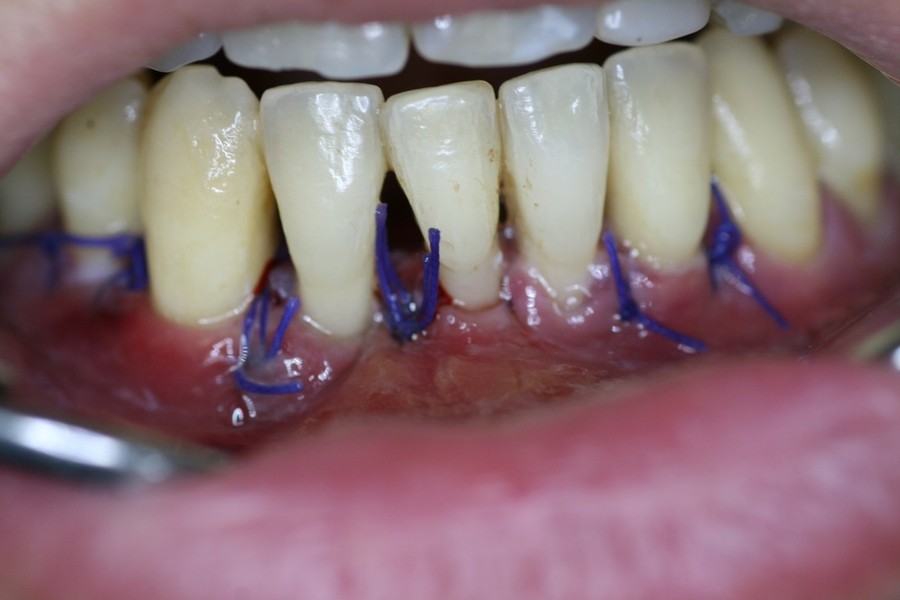

Chirurgia plastica Muco-Gengivale